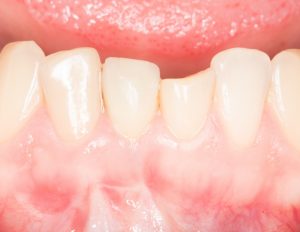

Рекомендации по установке имплантов. Для всех. Часть V.